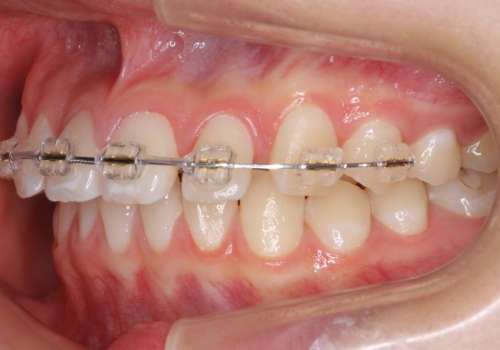

- ワイヤー矯正

- 9ヶ月

- 前歯のすき間を気にして来院。

全体矯正ではなく部分矯正で治療することになりました。

その代わり、すき間をすべて閉じるのは難しく、両脇の目立たないところに集めて治療終了しています。